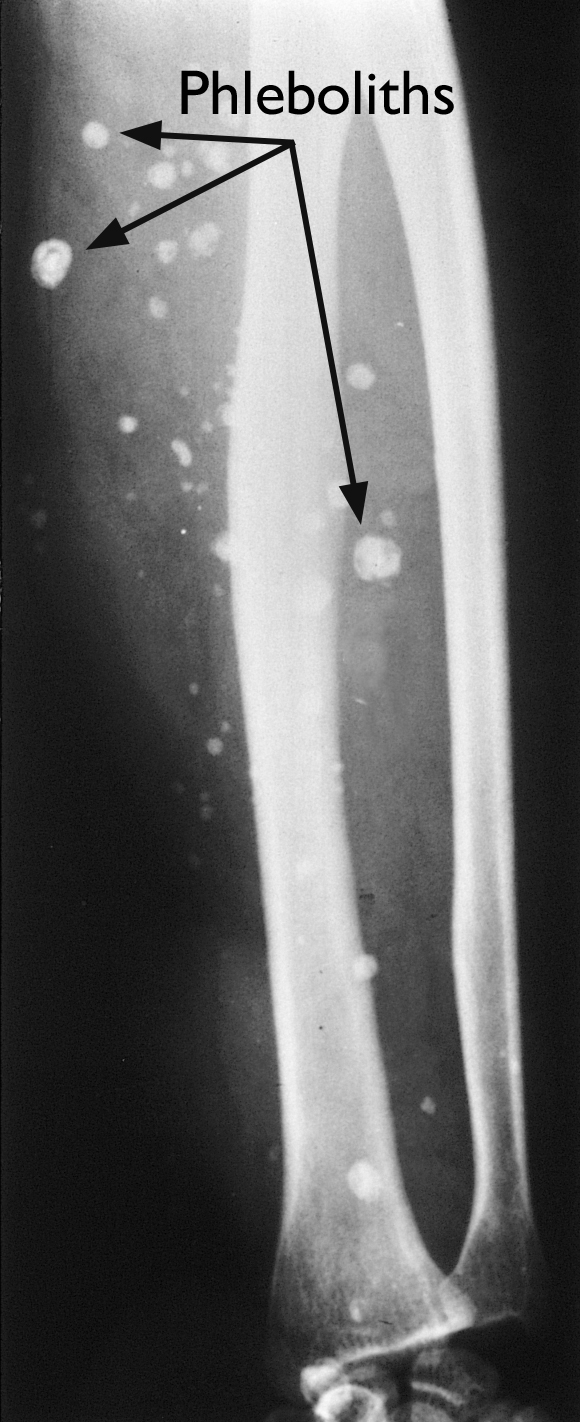

X-rays and computerized tomography (CT) scans. Although plain X-rays and CT scans are better for creating pictures of dense structures like bone, these imaging tests may show a cavernous hemangioma if it has calcifications (areas that have become hard, like stone; in fact, these calcifications are called phleboliths, which means "stone in the blood vessel" in Greek).

x-ray image of phleboliths

X-ray shows the small calcifications (phleboliths) inside the blood vessels of a cavernous hemangioma.

Reproduced from Johnson TR, Steinbach LS (eds): Essentials of Musculoskeletal Imaging. Rosemont IL. American Academy of Orthopaedic Surgeons, 2004, p. 155.